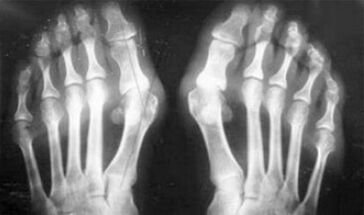

The difference between arthritis and osteoarthritis of the fingers and hands of the hands is that the first disease is cured and that the second is not.With arthritis, synovial shell and the joint capsule are affected.

The defeat of cartilage and bone tissue only occurs in late stages in a neglected state.With osteoarthritis, the cartilage fabric is first affected, then the bone, the inflammation of the synovial membrane is of secondary origin, that is to say that it develops on their history.